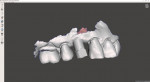

Four months after extraction, a CBCT scan and intraoral scan were acquired (Figure 2 and Figure 3), and the data was then used to place the virtual tooth and visualize the final restoration (Figure 4 through Figure 6). At this stage, when the quantity and quality of the bone is sufficient, the clinician can plan the implant placement. Bone grafting may be necessary in some cases, but for this patient, the bone allowed for ideal placement. After an implant was selected from the library, it was placed in the virtual planning software, and a surgical guide was created to facilitate its ideal trajectory (Figure 7 through Figure 9). The surgical guide was then fabricated on a 3D printer, which provided the necessary level of precision for it.

When the patient arrived on the day of surgery, the surgical guide fit perfectly (Figure 10). The implant was placed (Figure 11), followed by a healing abutment, and the patient entered a healing phase prior to receiving the final restoration. Over the course of approximately 3 weeks, the patient developed a good emergence profile. When she returned to the office for restoration, a scan body was placed, the site was scanned (Figure 12), and the scan data was imported into the CAD software (Figure 13). The final restoration was then designed on an abutment (Figure 14 and Figure 15) and milled from zirconia (Figure 16 and Figure 17). It was delivered and fit perfectly.